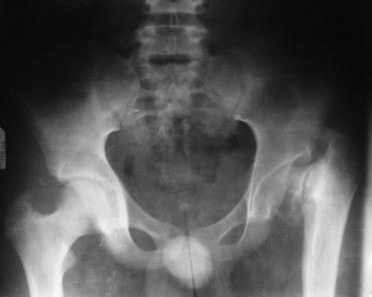

[Ortho] дисплазия тазобедренного сустава

Имя     : PICT0231.JPG